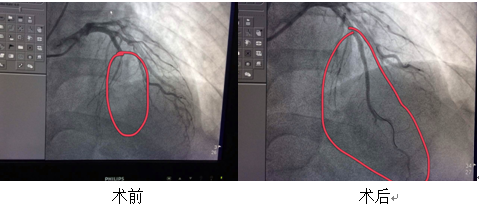

18:45患者到达我院急诊科,在准备充分的情况下,急诊与心内共同按照流程对患者进行处理,判定该患者急性前壁心肌梗死诊断明确,建议急诊介入治疗,同时DSA也准备完毕。虽然由于家属的原因延误30分钟左右,但在全体医护人员的努力下仍然为患者节省了大量时间。家属赶到医院,在了解病情及相关治疗方案后也非常配合,同意急诊介入治疗。19:40手术开始,造影显示患者前降支近段全闭,于19:55开通血管,并植入支架。整个手术过程顺利完成,术后患者胸痛明显缓解,生命体征稳定,入住心内科CCU病房进一步监护及治疗。